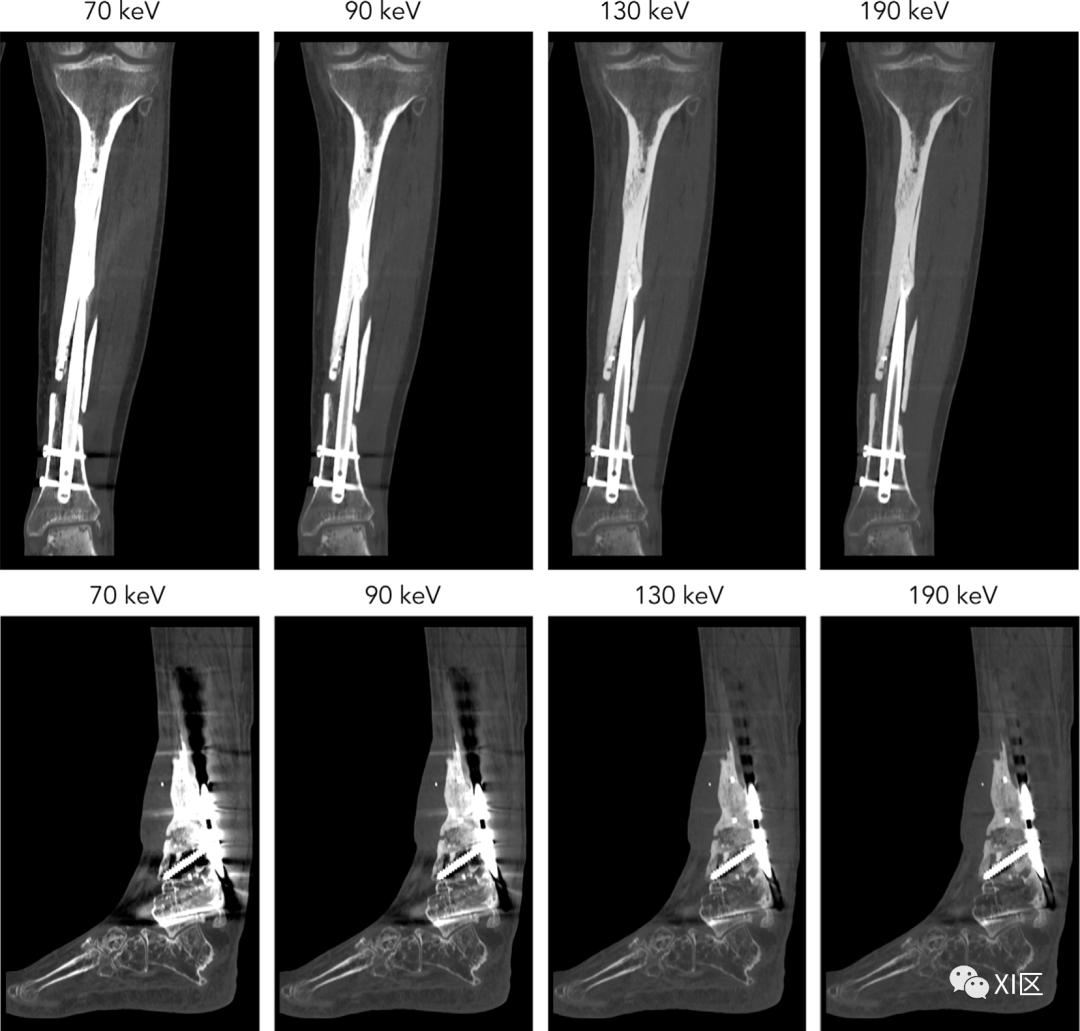

图9 患有肝细胞癌的64岁女性。由于肾功能不全(eGFR,21ml/min/1.73 m2),动脉期CT图像是以低对比剂剂量(220mgI/kg)获得。在70keV的虚拟单色图像(a)上,肝脏病变的可视化不够充分,而在40keV图像(b)和碘图(c)上可以清楚地检测到。当VMI的能量水平增加(即高于80 keV)时,组织之间的对比度降低,导致金属伪影减少。尽管如此,为了克服密集材料(如金属夹、线圈和支架)产生的严重伪影,可以使用专用的金属伪影减少软件(图10)。

图10 显示了从左至右分别以70、90、130和190 keV提取的单色图像:放置在胫骨中的钛髓内钉(上图)和用于固定胫骨远端不愈合和胫距关节融合术的不锈钢钢板固定(下图)。髓内钛植入物的伪影较少,在较高能量下几乎没有观察到伪影减少。对于不锈钢植入物,每增加一个能量都会导致伪影减少。关于单能谱临床价值的更多内容,参见:。